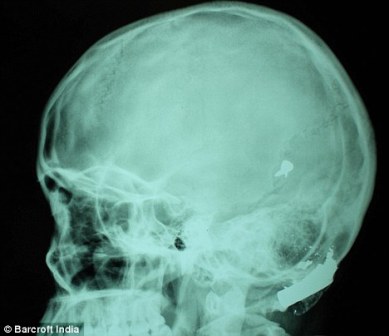

其中一顆子彈擊中她的左中耳,穿透了她的耳骨,然后擊中頭骨,嵌在了腦子里。另外兩顆子彈分別擊中她的右臂和心臟。印度Lok Nayak醫(yī)院的醫(yī)生稱(chēng),赫娜能夠康復(fù)完全是奇跡,她也足夠幸運(yùn)。她的主治醫(yī)生稱(chēng):“當(dāng)我們看到她的情況時(shí),被嚇了一跳,幸運(yùn)的是她活了下來(lái)!

這顆子彈沒(méi)有損壞大腦中控制身體機(jī)能的部分。盡管赫娜的手術(shù)很成功,但醫(yī)生表示,她還有出現(xiàn)感染和并發(fā)癥的可能。子彈毀掉了她的中耳,可能導(dǎo)致她耳聾。(楊柳)